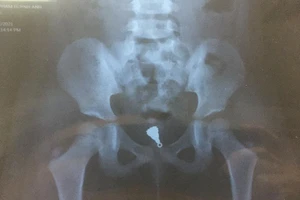

Gắp mặt dây chuyền nằm sâu trong âm đạo bé gái 5 tuổi